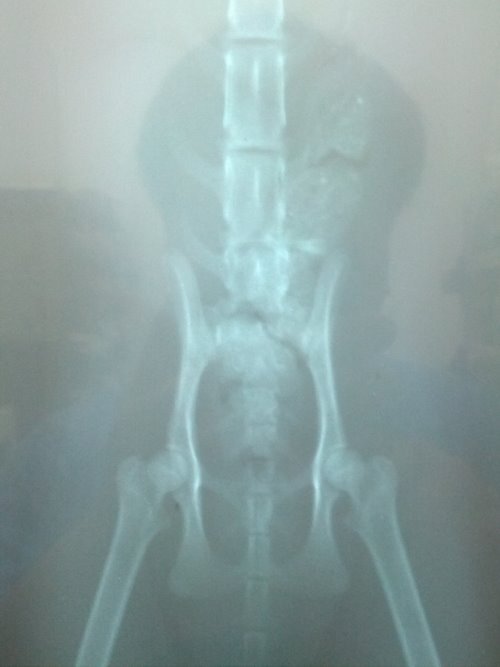

主題: 下半身癱瘓~求助 申請者姓名: Jason Yang 花色: 申請日期: 2013-06-07 00:05:28 申請者部落格: 申請者臉書網址: 所在縣市/合作醫院: 新北市/哲生動物醫院 治療費用: 6200元 需求人數: 8人 已結案 (2013-08-06 14:01:08) 報名人員: Chloe Liang(已付款)、alicelin(已付款)、Sean Chun-hsiang Yo、貓球球(已付款)、himawari(已付款)、himawari、himawari、Bei Yi Su(已付款)、Fei Lika Tsai(已付款)、Fu Nk(已付款)、Yvonne Chen(已付款)、 候補人員: 動物病情說明: 在我的工廠發現一隻玩到下半身不能動的貓,於晚上九點多發現,已詢問淡水之上哲動物醫院該如何處置~目前餵食罐與與放置鐵籠~已鋪設毛毯及紙箱~~明日將帶前往醫院檢查是否有救...

貓目前意識清楚~唯有腳~尾巴無法動作

貓咪檢查後發現第一薦椎骨折,造成後半身癱瘓,眼睛也有病變,經過六天治療,貓咪都不願意自己進食,精神很差,每天醫師都有幫他擠尿按摩腹部幫助他排便,治療不見改善,幾經考量,為減輕貓咪的痛苦,只好以人道的方式送貓咪一程,還請各位幫忙貓咪。謝謝!